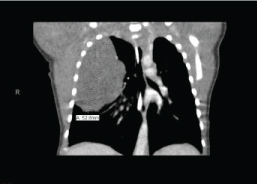

A 5-day-old, 2.6-kg male born at 36 weeks' gestation via c-section was noticed to have respiratory difficulty shortly after birth. Radiologic investigations revealed a right-sided chest mass with slight mediastinal shift (Figure 1). A diagnosis of CPAM was made, and the child was scheduled for right upper lobectomy. He was otherwise healthy with no abnormal laboratory or clinical findings. The case was discussed with the surgical team, and it was decided to proceed with lung isolation and single-lung ventilation (SLV). Atropine was administered intravenously, and anesthesia was induced with propofol and rocuronium. Mask ventilation was instituted using minimal pressures with 2% sevoflurane and 100% oxygen. Direct laryngoscopy (DL) was performed and a 4 Fr Fogarty embolectomy catheter (FC) easily inserted until resistance was met. An initial attempt with a 3.0 cuffed tube was met with resistance, and, subsequently, a 3.0 uncuffed endotracheal tube (ETT) was placed alongside the FC. A fiberoptic scope (FOS) was then advanced through the ETT, and we discovered that the FC had entered the unintended left main bronchus. We therefore withdrew the catheter and repositioned it into the operative (right) bronchus. The patient's oxygenation and ventilation were optimal at this point and blood pressure and heart rate within normal ranges. Several minutes thereafter, the end-tidal CO2 tracing diminished and then disappeared. Oxygen saturations then began to fall rather dramatically, and the child developed bradycardia. At this time, ETT position was confirmed and auscultation revealed minimal coarse sounds on the right and absent sounds on the left chest. Acute bronchospasm was suspected, and albuterol and epinephrine were administered. With no resultant improvement, pneumothorax was suspected. A stat portable radiograph was ordered; however, given the rapidly deteriorating condition of the child, it was decided not to wait for the radiograph but place the chest tube entirely on clinical grounds (Figure 2). Immediately upon decompression, we were able to reestablish ventilation and ETCO2 tracing reappeared and oxygenation improved. Hemodynamic parameters returned to physiologic range. In view of the life-threatening episode that had occurred and nonurgent nature of the procedure, a decision was made to postpone surgery. The child was transported back to the neonatal intensive care unit intubated and ventilated in stable condition.

Figure 1: CT of the chest with contrast showing congenital pulmonary airway malformation in the right lung. View Figure 1